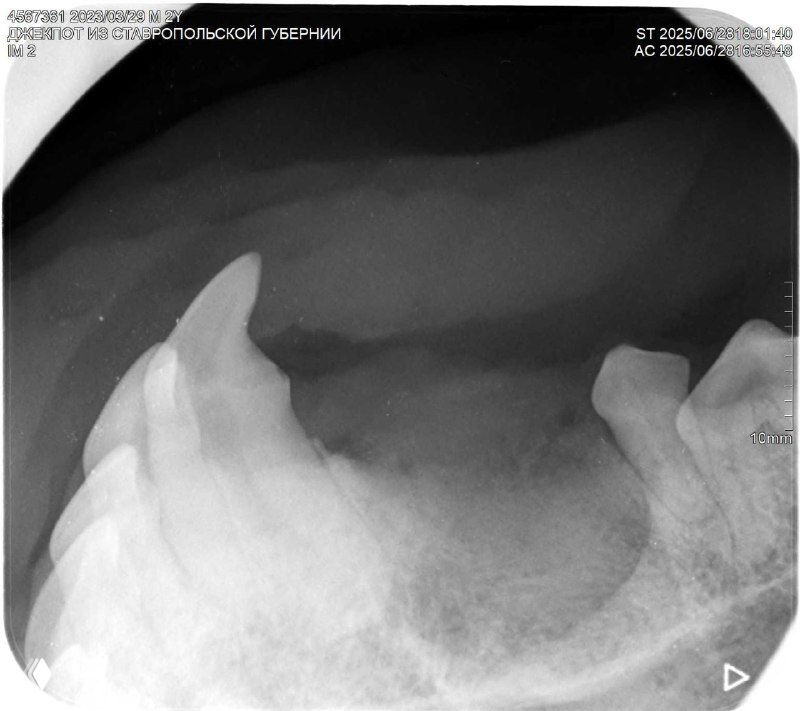

На снимках видно, какой ОГРОМНЫЙ корень у клыка - больше, чем видимая часть 😱